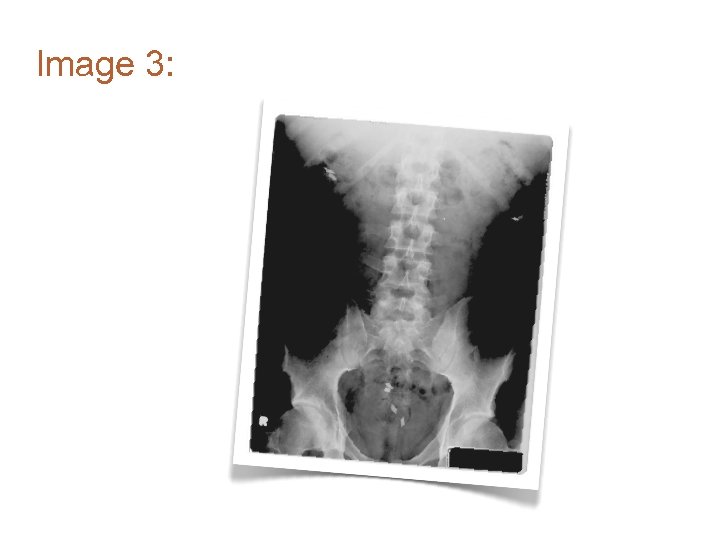

Image 2: